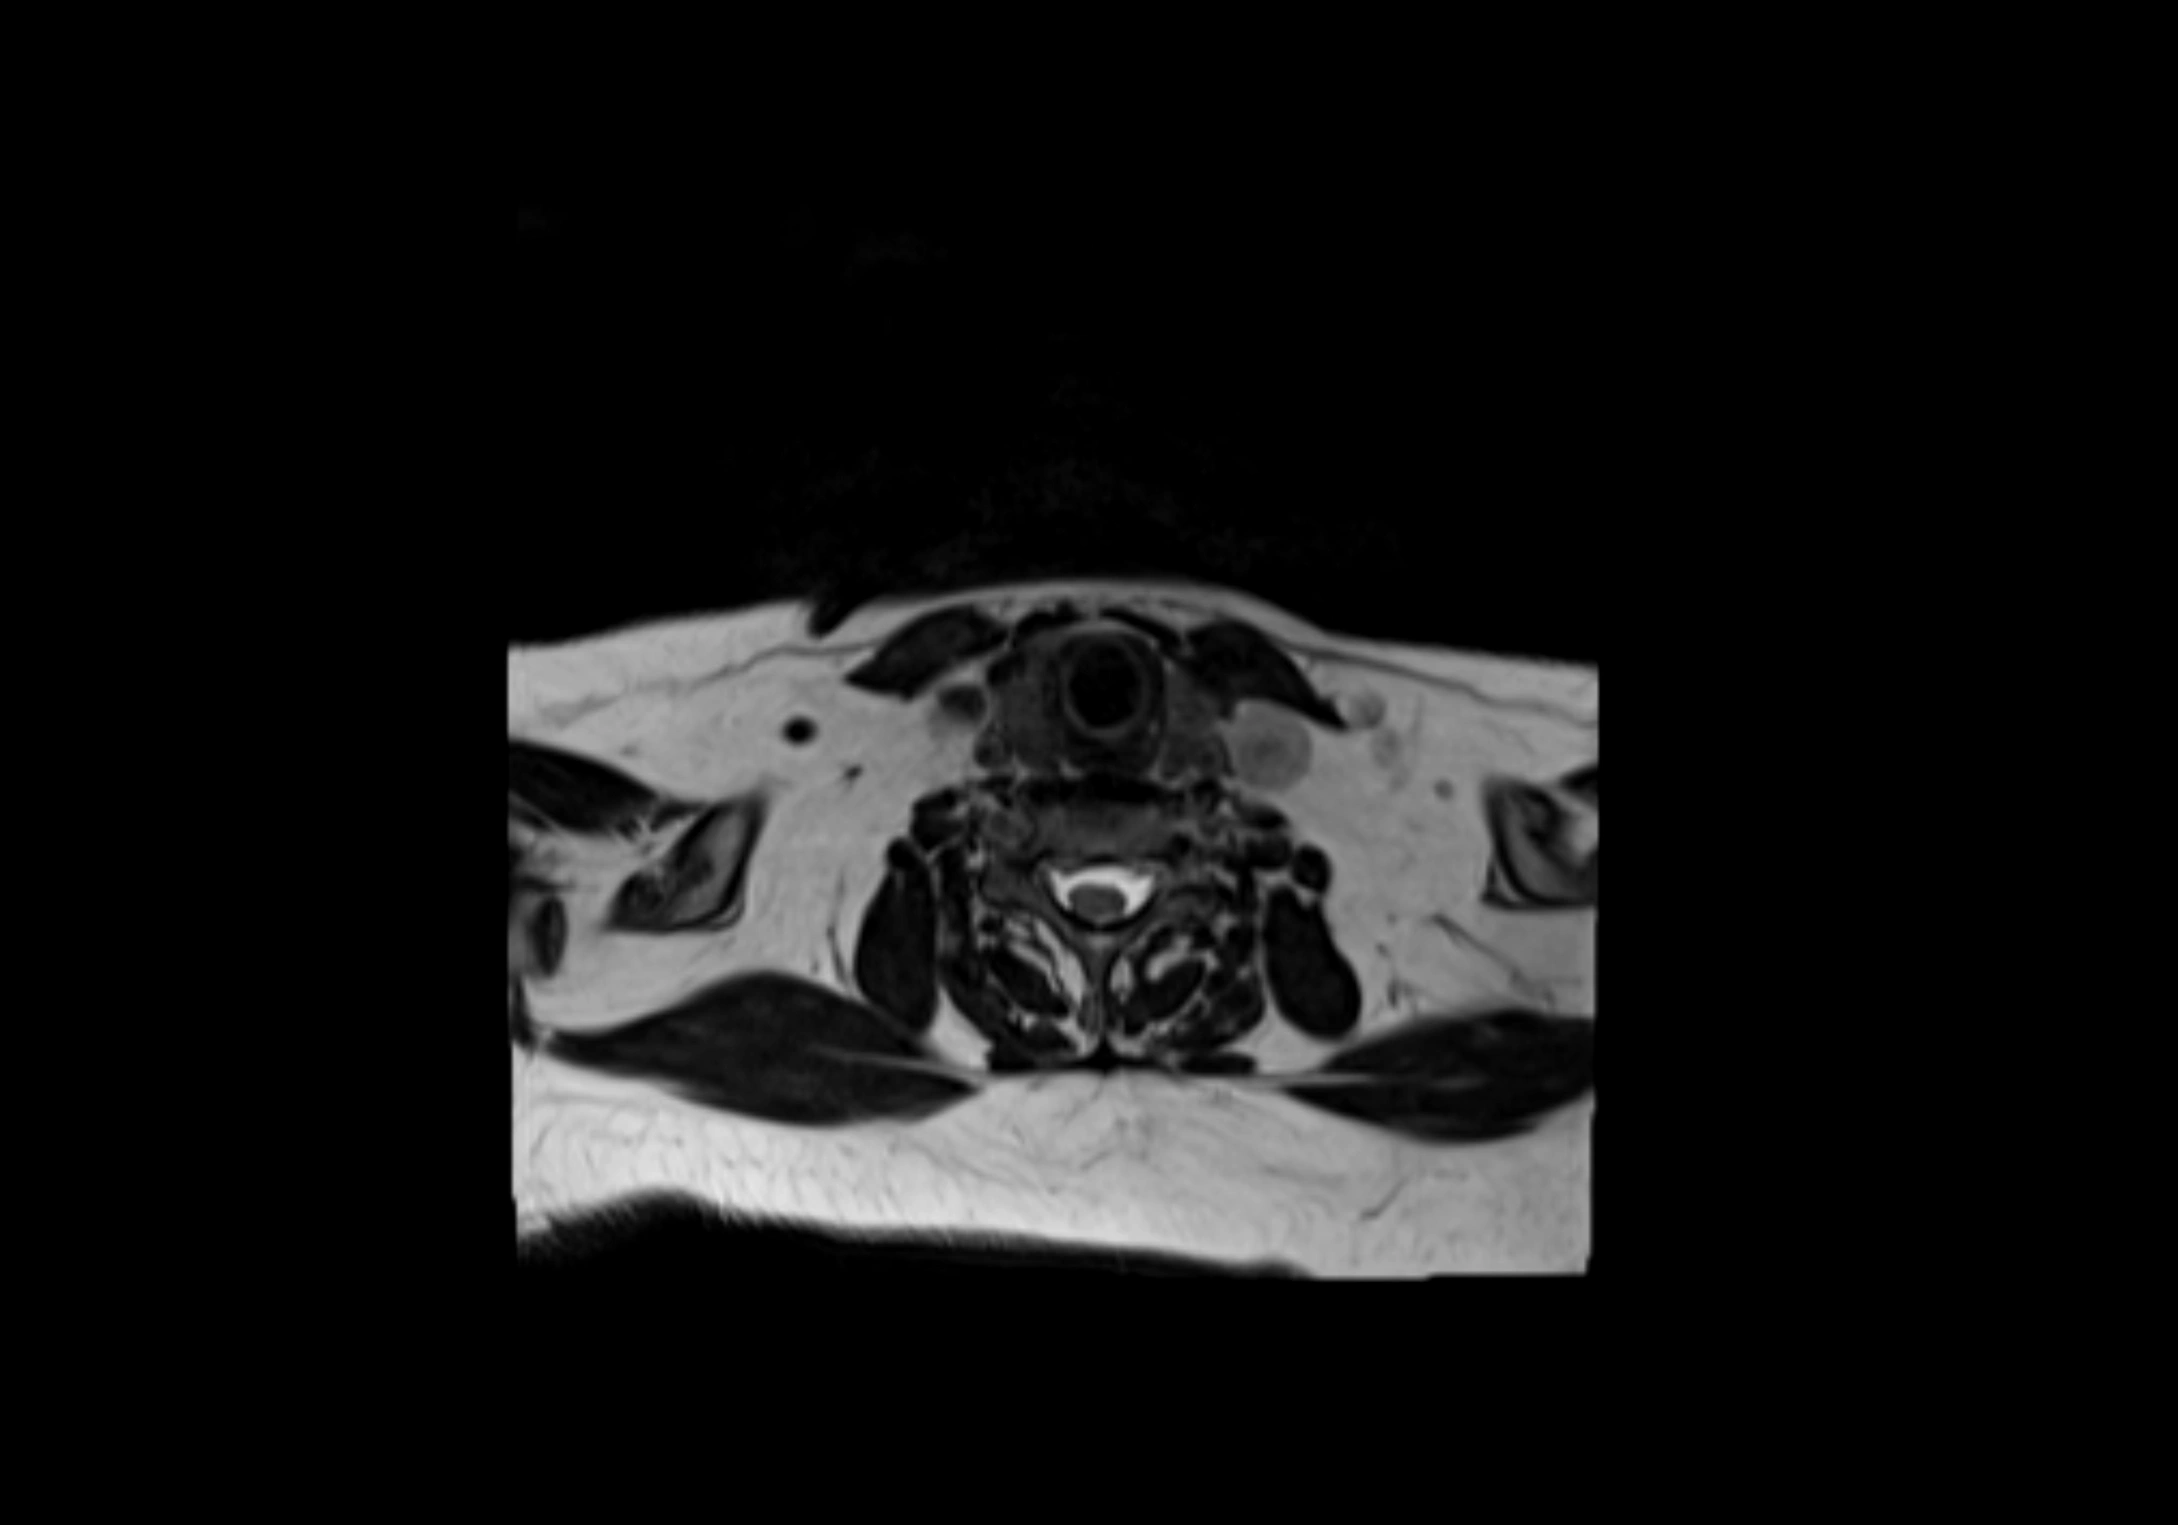

MRI Appearance

T1-weighted images:

• Normal accessory nodes appear as small, oval hypointense to intermediate signal structures within subcutaneous fat

• Surrounded by hyperintense fat, enhancing contrast for visualization

• Pathological nodes may appear enlarged or rounded, sometimes with cortical thickening